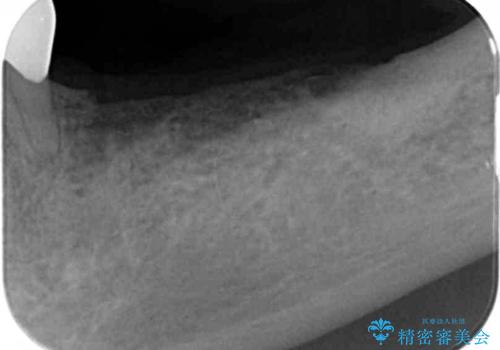

- 長年使っていた入れ歯をなくしてしまい、これを機にインプラントにしようと思い立ち来院されました。

通常長年インプラントを使用すると骨が吸収しインプラント治療が難しくなることもありますが、十分な骨が残っていたためすぐにインプラントの埋入計画を立てることができました。